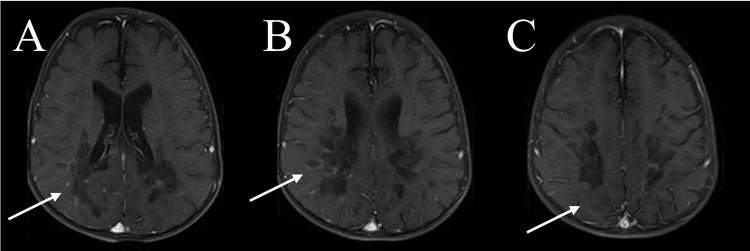

Case presentation: We present a case of a 10-year-old boy with ALD who presented with seizures, progressive weakness, visual impairment, and adrenal insufficiency. Despite symptomatic management and dietary adjustments, the disease progressed rapidly, leading to respiratory failure and eventual demise. The diagnosis was confirmed through molecular analysis and elevated VLCFA levels. Neuroimaging revealed characteristic white matter changes consistent with ALD.